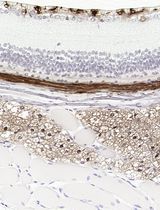

采用 Davidson 固定液和黑色素漂白法优化小鼠眼组织切片的免疫组化染色

Anne Nathalie Longakit [...] Catherine D. Van Raamsdonk

2025年11月20日 1625 阅读